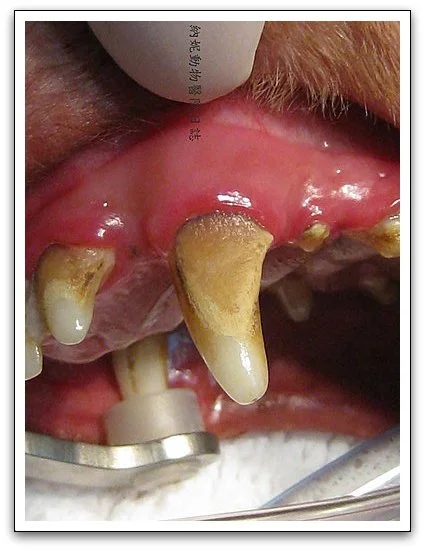

- 許多牙結石會導致牙齦萎縮,使狗貓的牙根外露

- 外露的牙根會使食物更容易堆積,在難以清潔的區域產生更多牙結石

大家可以清楚看到這隻狗狗的牙齒狀況,以及牙結石的累積程度。